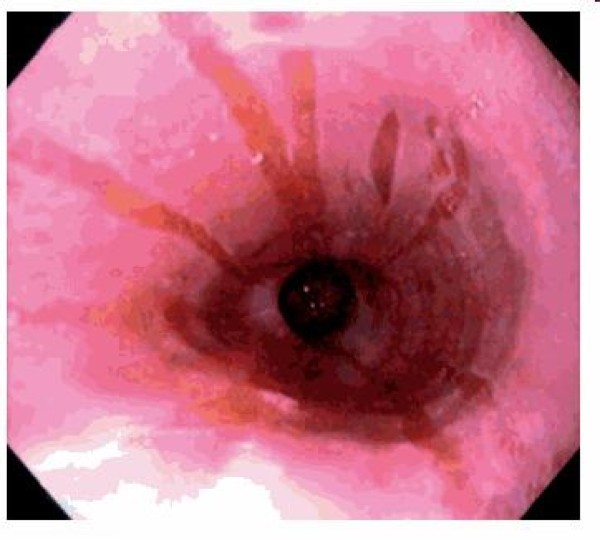

A 55 year old obese man reports frequent chest pain, especially after eating spicy foods or drinking coffee. What is his diagnosis based on the endoscopic exam and what are the complications of this condition?

GERD: see hyperemia, vertical linear streaks due to mucosal erosions/ulcers

Pathogenesis:

Associated symptoms: Regurgitation, pulmonary symptoms (adult-onset asthma), cough (at night), hoarseness, laryngitis, chest pain, disturbed sleep

Lab tests:

1) 24-hour ambulatory esophageal pH monitoring= gold standard (measures proximal and distal esophagus, stomach pH)

2) Endoscopy (with biopsy)- rule out other pathology, look for Barrett’s

3) Bernstein test= reproduce patient’s symptoms by infusing acid into esophagus

Complications: Esophagitis–> peptic stricture, esophageal hemorrhage, ulcer, pulmonary symptoms, Barrett’s esophagus